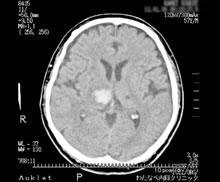

脳出血や脳梗塞は、ある日ある時突然に、脳の血管が切れて出血したり、詰まってしまう(梗塞)ことで、色々な障害が生じます。障害された場所により症状が異なります。同じ側の手足がマヒしたり、感覚障害(シビレや痛み)がみられたりします。また、呂律が回らなくなったり(構音障害)、言葉が理解できるのに話せなくなる(失語症)ことや、ものが二重に見えるなどの様々な症状を呈します。診断は急激な発症かどうかということを考慮し、神経学的診察所見および頭部CTなどの画像診断から判断します。

突然、頭を抱えて頭痛を訴えた後で倒れてしまった人を目の前にしたら、くも膜下出血と決めて救急車を呼ぶべきであるぐらい、特徴的な症状と言えます。くも膜下出血では、脳表面のクモ膜下腔に出血がみられ特徴的なCT所見を呈します。出血が軽度でCT上、特徴的な所見が見つからない場合、腰に長い注射針を穿刺し、脳脊髄液に血液の混入があるかどうかを確かめる必要があります。経験のない突然の強い頭痛が見られた場合には、念のため医療機関の受診をお勧めします。